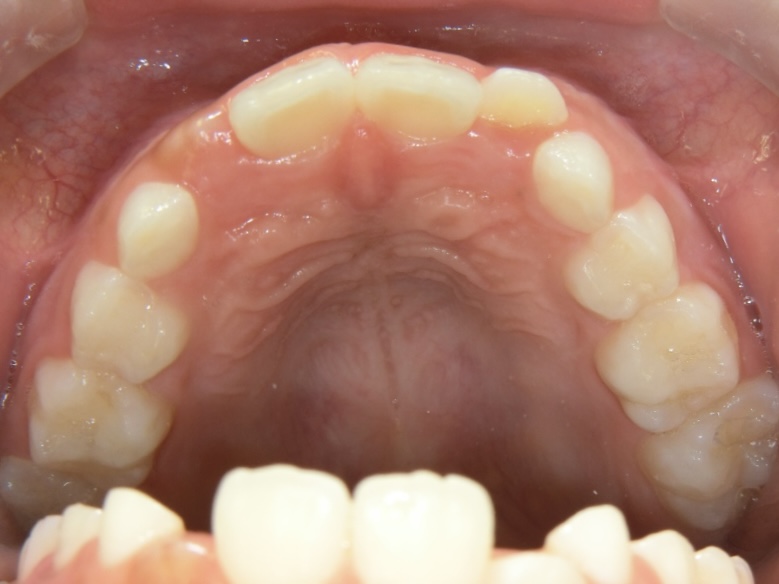

Before 1

Before 2

Before 3